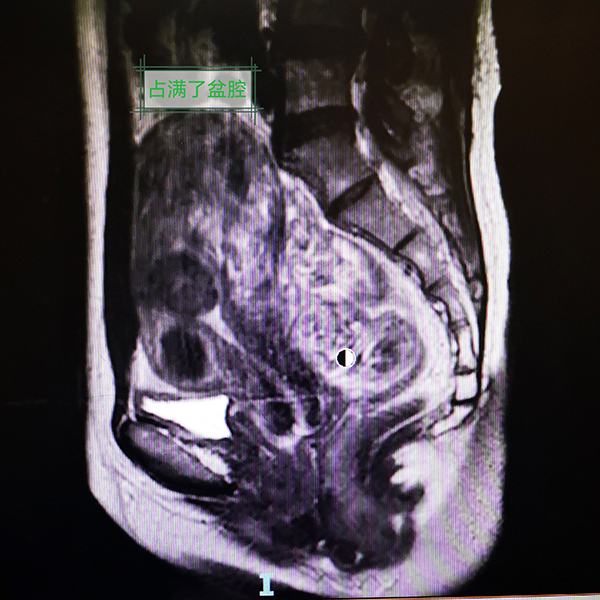

入院后,小楊進一步完善了腹部MRI等相關檢查,結果顯示她的病情比醫生預知的情況更復雜。小楊的陰道只有約1cm長,宮頸陰道全程實性梗阻;盆腔增強磁共振考慮宮頸、陰道發育異常,宮頸閉鎖可能,伴宮腔積液/積血;左下腹-盆腔內良性囊性腫塊,考慮左側附件來源病變,出血性囊腫可能;雙側輸卵管擴張、積液/積血;考慮盆腔包裹性積液,伴盆腔腹膜滲出改變。經過多學科聯合診療,醫生決定為小楊實施經陰道陰道成型術+宮頸探查+成型術+腹腔鏡探查+左側卵巢囊腫剔除+雙側輸卵管傘端造口+腸粘連松解術。

此次手術復雜且難度高,由在生殖道畸形手術方面具有豐富經驗的楊嵐副主任醫師團隊實施。術中,醫生看到小楊盆腔內廣泛粘連、多發包裹性積液(陳舊性血液),雙側卵巢見多個巧克力囊腫,雙側輸卵管明顯充血腫脹,子宮明顯增大。陰道口探入最深1cm,之后陰道結構完全封閉消失形成盲端,未見宮頸結構。在腹腔鏡的直視下,B超引導下探針進入宮腔,陳舊的巧克力樣積血噴涌而出,殘留4年的經血終于順利流出。同時,腹腔鏡下手術逐漸恢復小楊的正常解剖結構。反復下腹痛的“老問題”終于解決了,術后小楊說自己終于睡了個好覺,她母親臉上也露出了久違的笑容。